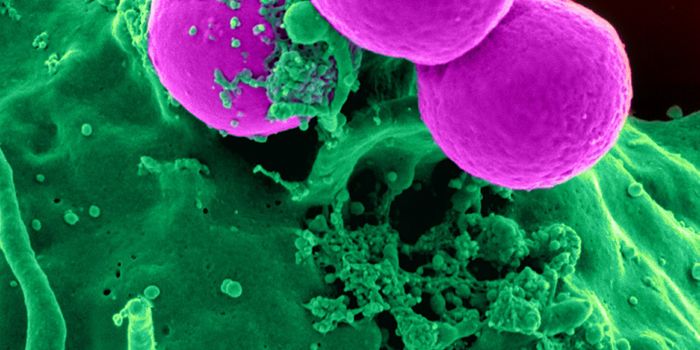

AUG 23, 2017ImmunologyA bacterium called Staphylococcus aureus is arguably one of the world’s most dangerous superbugs. It made The Worl ...